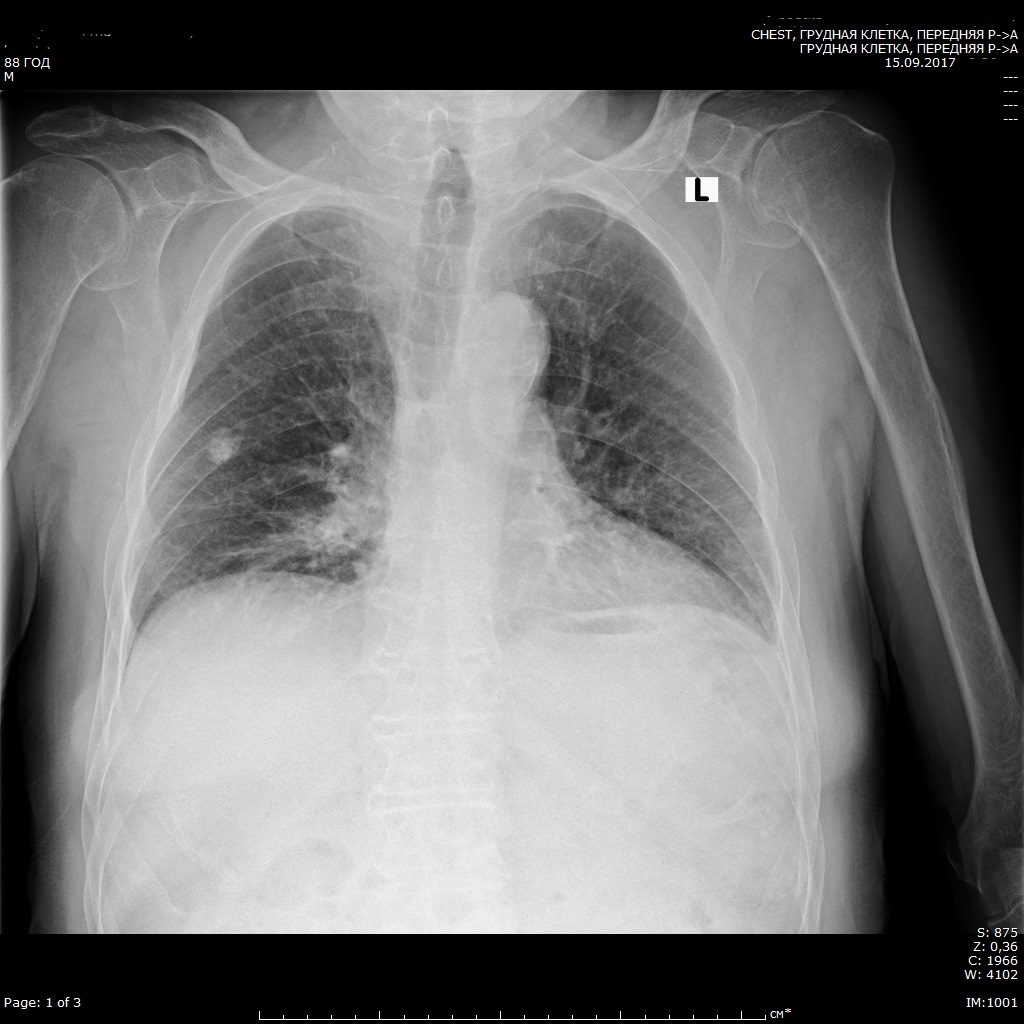

Снимок легких при туберкулезе является важным методом диагностики этого заболевания. На рентгеновских снимках можно увидеть изменения в легких, которые свойственны туберкулезу.

Фотографии снимков легких при туберкулезе

В данной статье представлены многочисленные фотографии снимков легких при туберкулезе, чтобы помочь вам понять, как выглядят изменения легких на рентгеновских снимках при этом заболевании.